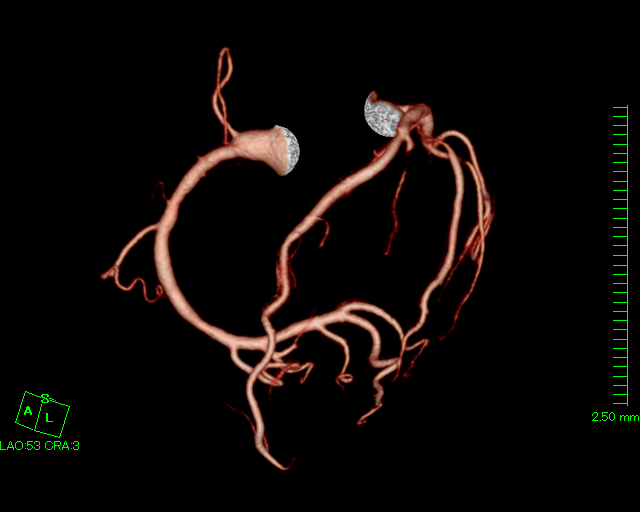

| 冠動脈CT検査 |

造影剤を使用し、心臓の血管(冠動脈)を撮影します。心臓は拍動しているので、心電図と同期させ高速に撮影します。 撮影した画像をワークステーションで処理することで、冠動脈の3D画像を作成したり、冠動脈の状態を確認できます。主に冠動脈の狭窄が疑われる患者様に行います。 |